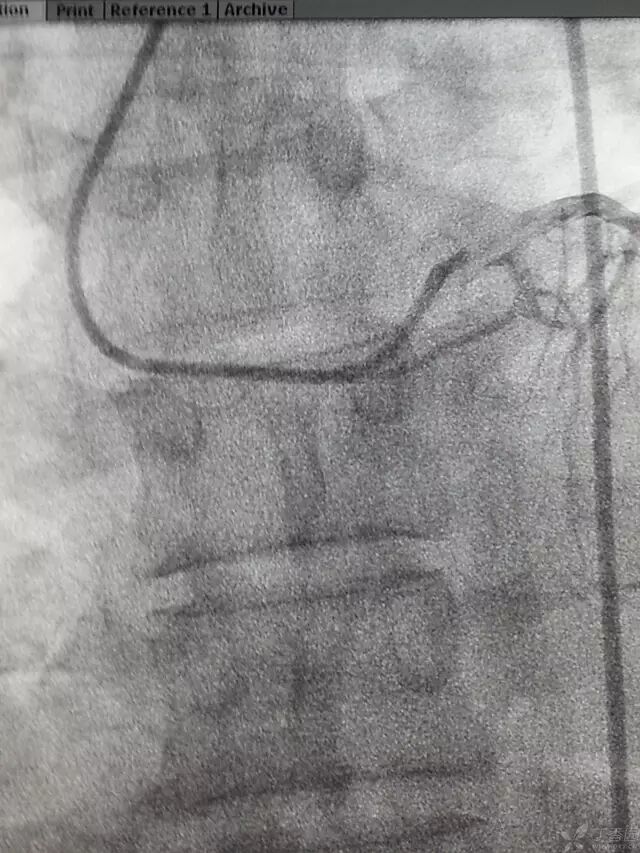

将造影导管头端塞入鞘管头,助手送入导丝,当外露导丝 10-15 cm时,踩线,小步快走送入造影导管,当进入锁骨下动脉时,如下图。

造影导丝是什么原来心脏造影这样做:冠脉造影全程图解_https://www.jmylbn.com_新闻资讯_第11张